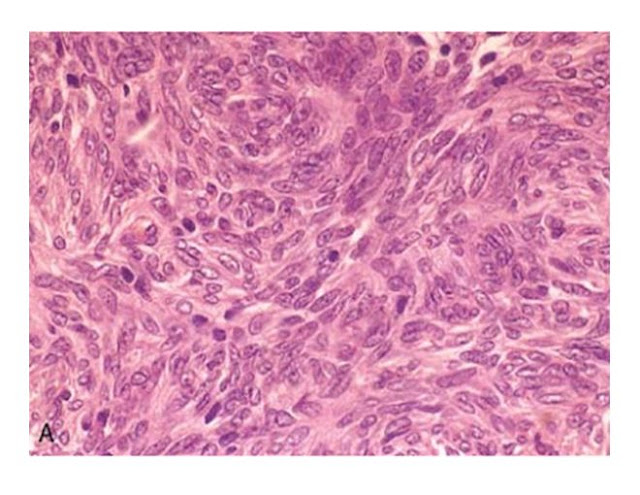

Diffuse large B-cell lymphoma. Tumor

cells have large nuclei, open chromatin, and prominent nucleoli. (Courtesy of

Dr. Robert W. McKenna, Department of Pathology,

University of Texas Southwestern Medical

School, Dallas, TX.)

The malignant lymphocytes here are very

large with a moderately abundant cytoplasm, and the nuclei are round to ovoid

with prominent nucleoli and occasional mitoses. The diagnosis is diffuse

malignant lymphoma, large cell type (also known as: immunoblastic lymphoma).